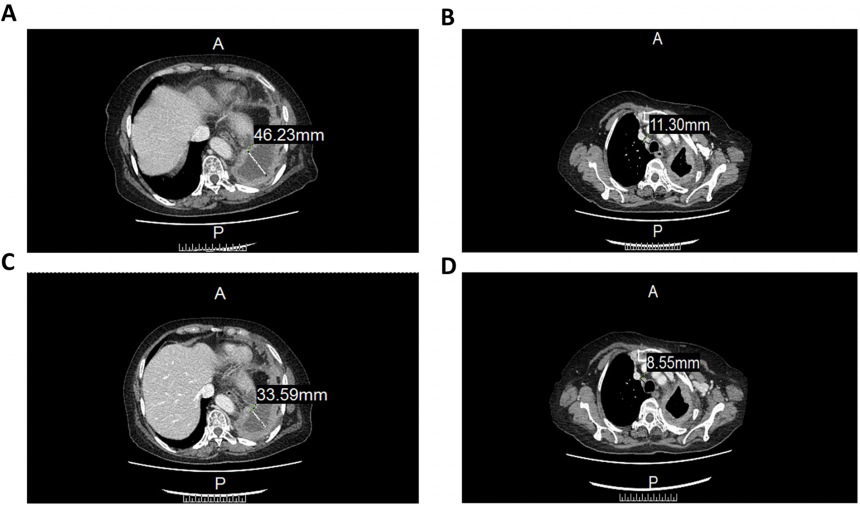

出现严重症状后,对患者血清细胞因子水平的分析表明,干扰素-γ和肿瘤坏死因子α(TNF-α)的表达在第八次治疗时达到峰值(图1)。CT图像显示细胞疗法对治疗肿瘤有一定疗效。具体而言,左肺包裹的胸内液体从46.22 mm减少到33.59 mm(图2A,C),而前气管后腔静脉间质区的淋巴结从11.3 mm减少到8.55 mm(图2B,D)。CT图像显示右肺结节明显大于基线结节(图3)。尽管患者的病情逐渐稳定,但经过一系列对症治疗后,考虑到严重副作用的可能性,她选择退出了这项临床试验。

图1. CCCR-NK92细胞治疗前后纵隔窗的CT图像。(A)CCCR-NK92细胞治疗前的CT图像。(B-C)CCCR-NK92细胞治疗一个周期后的CT图像。(D)细胞治疗两个周期后的CT图像